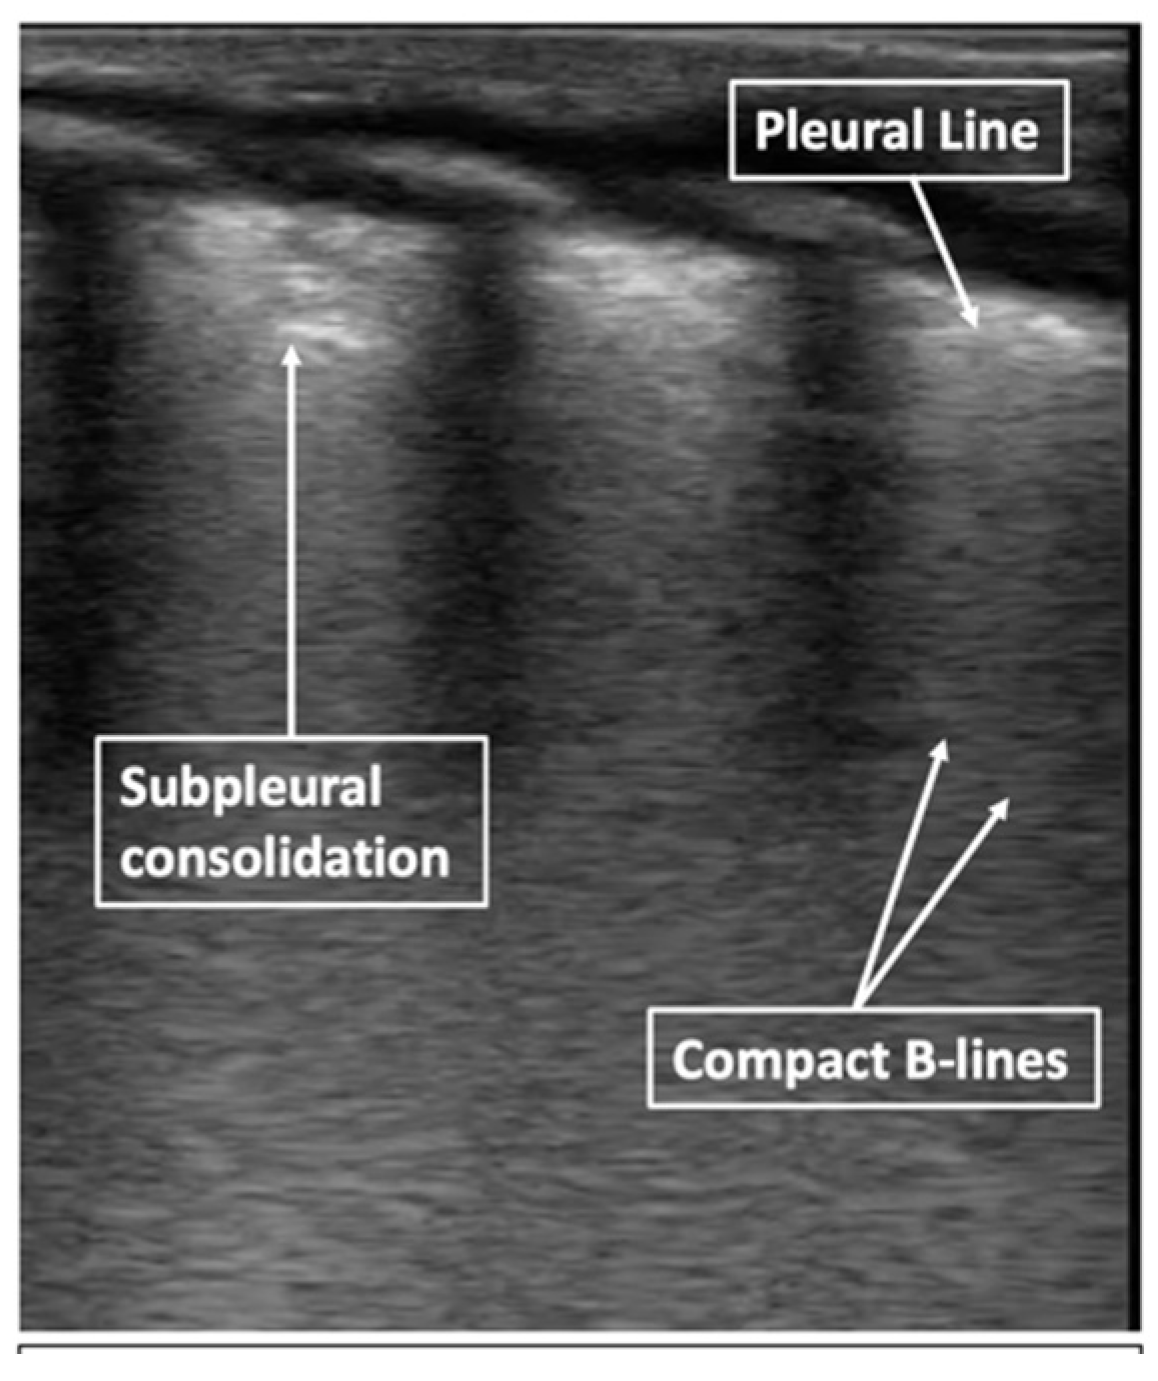

2.5. Respiratory Distress Syndrome

Predicting the Need for Intervention with Respiratory Distress Syndrome

2.6. Bronchopulmonary Dysplasia

Predicting the Development of Bronchopulmonary Dysplasia